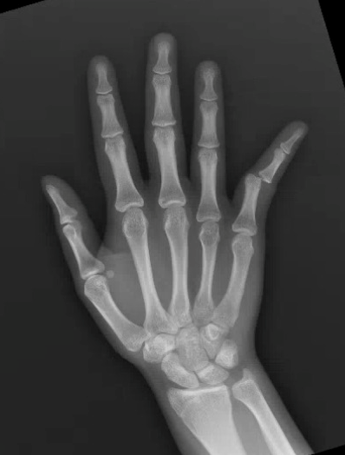

A 13 year old female presents with right 5th digit pain and deformity after she hyperextended her finger while catching a basketball. What's the diagnosis? (scroll down for answer)

Answer: Proximal interphalangeal joint dislocation

Mechanism - hyperextension or axial load

-Usually ulnar deviation as radial collateral ligament more likely to rupture (as in this case)

-May be dorsal (associated with volar plate rupture, can lead to Swan neck deformity) or ventral